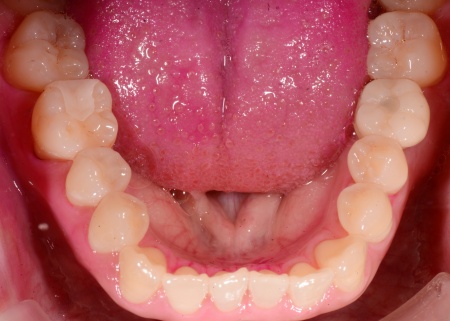

治療後

| 行った治療内容 | 診断結果を丁寧にお伝えしたうえで、左下奥歯の抜歯に同意いただきました。 抜歯後に歯を補う方法として、以下の3つを提案しました。 ①インプラント治療 あごの骨に人工歯根を埋め、その上に人工歯を装着する方法 メリット:自然な見た目と噛み心地が期待できる デメリット:自費診療のため費用がかかる。外科処置が伴うため身体的な負担がある。治療期間が比較的長くなる ②ブリッジ治療 前後の歯を削り、橋渡しのような被せ物で歯を補う方法 メリット:保険診療内でも治療が可能。外科手術を行わずに安定した噛み心地を実現でき、取り外しも不要 デメリット:前後の健康な歯を削る必要がある ③取り外し式の入れ歯 メリット:保険診療内でも治療でき、治療期間も比較的短い デメリット:毎日取り外して手入れをする必要がある。自分の歯や他の方法と比べて噛み心地が劣る傾向がある それぞれのメリット・デメリットを丁寧にお伝えしたところ、患者様は①のインプラント治療を選択されました。 【治療手順】 ①左下奥歯を抜歯すると同時にインプラント埋入手術を行う「抜歯即時埋入」を実施。インプラントを正しい位置と角度であごの骨に埋入する ②インプラントがあごの骨に問題なく定着したことを確認してから型取りを行い,インプラントの上に取り付ける人工歯を作製・装着する ③最後に、装着した人工歯が自然な仕上がりでしっかり噛めることを確認して治療を終了 |

| 治療期間の目安 | 約5ヶ月 |

| おおよその費用 | 510,000円 |